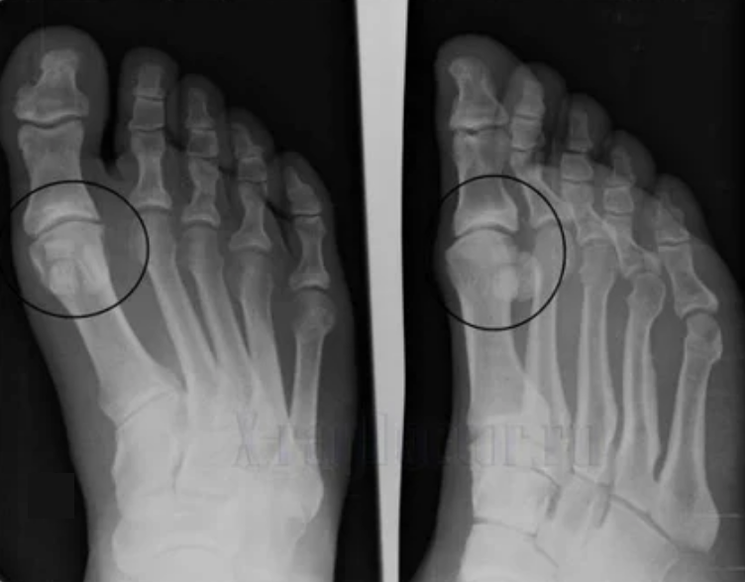

Um eine Diagnose zu stellen, untersuchen Rheumatologen die Beschwerden des Patienten und verschreiben eine X -Ray -Untersuchung. Meistens wird die Radiographie in 2 Projektionen verwendet. Der Arzt untersucht das Vorhandensein dystrophischer Störungen bei hyalinen Knorpel- und Knochenfugen. Wenn die Gelenkspalt verringert ist, sind die Knochen deformiert oder abgeflacht, es gibt zystische Formationen auf der Oberfläche des Knorpels, Osteophyten sind offensichtliche Anzeichen von Arthrose. Während der Inspektion zeigt die Arthrose die Instabilität des Gelenks an: Die Achse der Gliedmaßen und Subluxation wird gestört.

Oft ist ein X -Ray -Bild nicht in der Lage, vollständige Informationen über den Zustand des Gelenks zu geben. Für eine gründlichere Studie wird die Computertomographie verschrieben, und es ist wirksam, Knochen zu untersuchen. MRT wird häufiger zum Untersuchung von Weichgeweben verwendet.

- Reduzierung der Lücke in der Lücke des Gelenks, die auf dem Bild spürbar wird. Das Stadium des Verstoßes wird vom diagnostischen Tantgenologen bestimmt. Der Patient spürt die Komplexität oder Unfähigkeit, das Glied vollständig zu begradigen und zu biegen.